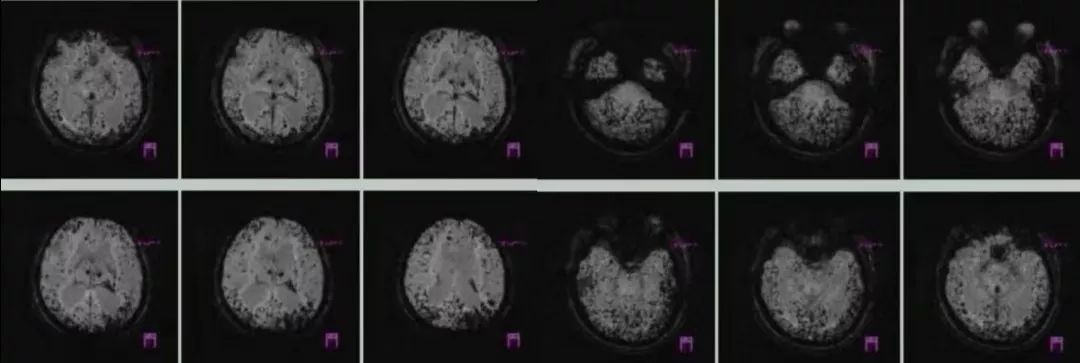

病例9

男性,62岁,因头痛,反应迟钝2月入院,既往有脑梗死病史。

答案:脑淀粉样血管病。

脑淀粉样血管病(Cerebral amyloid angiopathy,CAA)是一种以皮层和软脑膜血管壁内 β 淀粉样蛋白沉积(Amyloid-beta,Aβ)为特征的脑小血管疾病。CAA 是除高血压外,导致老年人脑出血的常见原因。CAA临床表现:脑叶出血,皮质微出血,皮质浅表含铁血黄素沉积/ 局灶性凸面蛛网膜下腔出血( SAH) ,皮层梗死和白质缺血性病变,痴呆,CAA相关炎症,淀粉样发作。淀粉样发作又称短暂性局灶性神经系统发作(transient focal neurological events,TFNE),作为无脑叶出血的脑淀粉样血管病患者的主要临床表现之一,与局灶皮质小灶出血有关,近年来已经逐渐被认为是CAA的另一个重要的临床特征。部分TFNE表现为"阴性"症状,如发作性的偏瘫或失语等,与经典的TIA发作极其类似,临床需要仔细鉴别。

CAA 的确诊只能基于脑血管中淀粉样蛋白沉积的活检证据。根据修改后的波士顿诊断标准,临床和影像学检查结果可以诊断出“可能CAA”。MRI的发展提高了我们检测“出血迹象” 的能力。当脑叶出现大量出血或微出血,其他原因被排除时,即使在没有组织病理学证实的情况下,也应归类为“可能 CAA”。